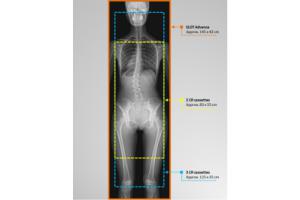

- Лучевая диагностика

Визуализация Shimadzu